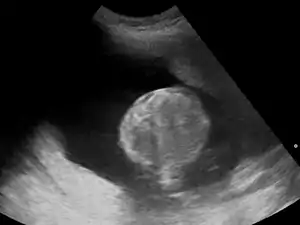

- sacrococcygeal teratoma

In most cases, the exact cause cannot be identified. A single case may have one or more causes, including intrauterine infection (TORCH), rh-isoimmunisation, or chorioangioma of the placenta. In a multiple gestation pregnancy, the cause of polyhydramnios usually is twin-to-twin transfusion syndrome. Maternal causes include cardiac problems, kidney problems, and maternal diabetes mellitus, which causes fetal hyperglycemia and resulting polyuria (fetal urine is a major source of amniotic fluid).